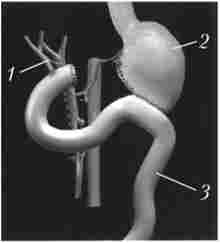

Локальна інвазія прилеглих вісцеральних судин ускладнює і нерідко робить неможливим виконання резекції у великого числа хворих на рак ПЖ, тому дООНераціонной діагностиці пухлинного проростання судин, особливо ворітної вени, надається велике значення (рис. 21.4). У комбінації з внутрішньовенним болюсним контрастуванням і субтракційної обробкою даних можна реконструювати СКТ-ангіограми, які відтворюють проекційні тривимірні зображення пухлини і судинного русла, визначити резектабель- ність пухлини з точністю 56-78%. Вважається, що результати СКТ можна порівняти з такими при спільному застосуванні КТ і ангіографії.

Спіральна комп'ютерна томографія з портографіей

Мал. 21.4. Спіральна комп'ютерна томографія з портографіей.

Рак головки підшлункової залози:

1 - гіподенсная горбиста пухлина головки підшлункової залози 4x5 см;

В В - контрастував паю воротная вена, яку проростає пухлина